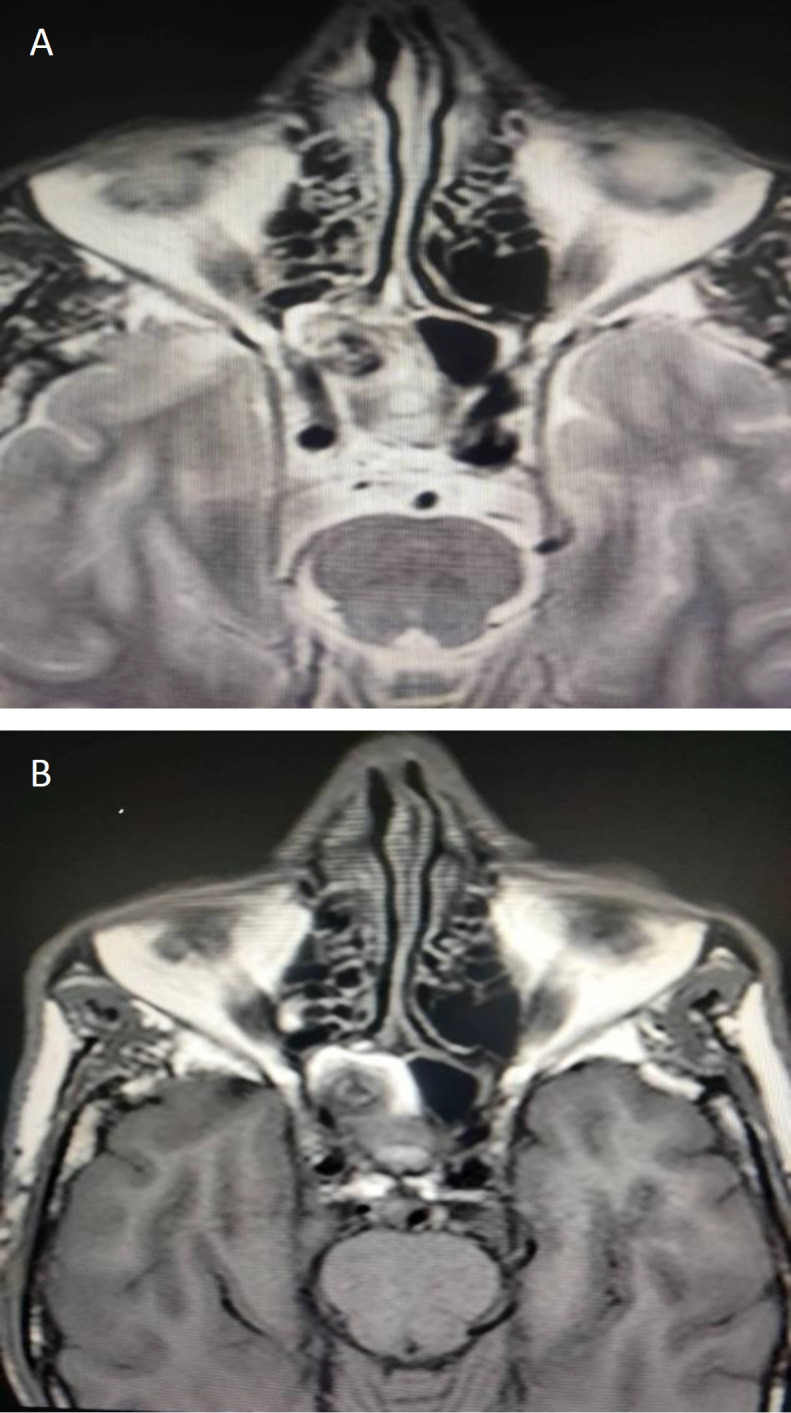

Case report: We report a case of a 57- year old male presenting with recurrent episodes of epistaxis. Contrast-enhanced Computed Tomography of the Paranasal Sinuses and Magnetic Resonance Imaging were performed, which showed a focal defect in the posterolateral wall of the sphenoid sinus through which an aneurysm from the cavernous segment of the Internal Carotid artery was seen herniating into the sinus with an associated hematoma.